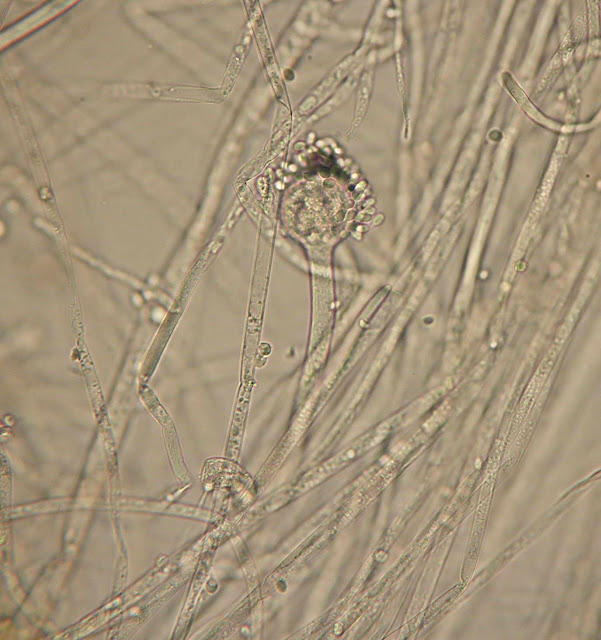

CUNNINGHAMELLA BERTHOLLETIAE (caso clinico nº2)